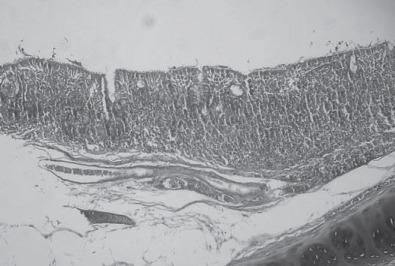

Infectious bronchitis is caused by a coronavirus, infectious bronchitis virus (IBV). Infectious bronchitis is an acute and highly contagious disease of economic importance due to the reduction in weight gain observed with infected broilers and the drop in egg quality and production associated with infected laying hens. The presence of deep pectoral myopathy has been associated with IBV variants. This lesion is detected at slaughterhouses and is characterized by paleness and atrophy of the deep pectoral muscle, including necrosis of the region, leading to condemnations of the breast muscle, a valuable meat cut in the market. This work aimed to study the relationship between deep pectoral myopathy and IBV by describing tracheal and muscle lesions and comparing the frequency of IBV detection via reverse-transcription (RT) PCR in muscle, tracheal, and cecal tonsil samples from broilers with and without myopathy. A case-control study was conducted in 40 broiler flocks vaccinated with the Massachusetts strain. The case group consisted of 23 flocks that presented myopathic lesions under sanitary inspection and a control group of 17 flocks without myopathic lesions. The tracheal, cecal tonsil, and supracoracoid muscle (with and without lesions) samples from the 40 broiler flocks were screened by RT-PCR to detect IBV. Histopathology of muscle and tracheal tissue was carried out. Upon microscopic examination, the muscle samples from the case group presented extensive necrosis, intense mononuclear inflammatory infiltration, muscle fiber fragmentation, and fibrotic tissue, confirming myopathy, whereas muscles from the control group showed no alterations. The tracheal samples presented a large number of infiltrated mononuclear inflammatory cells that in some areas formed submucosal nodules. A total of 25 flocks tested IBV positive by RT-PCR: 14 from the case group and 11 from the control group. The IBV was detected by RT-PCR directly in muscle samples. Despite that, the relationship between deep pectoral myopathy and IBV was not established. The higher positive IBV RT-PCR percentage noted in the cecal tonsil samples demonstrates how important the choice of organs is for diagnostic purposes.

传染性支气管炎由冠状病毒,传染性支气管炎病毒(IBV)引起。传染性支气管炎是一种具有重要经济意义的急性和高度传染性疾病,因为感染肉鸡的体重增加减少,以及感染产蛋鸡的鸡蛋质量和产量下降。深胸肌病的存在与 IBV 变异有关。这种病变在屠宰场被发现,其特征是深胸肌苍白和萎缩,包括该区域的坏死,导致胸肌被谴责,这是市场上有价值的肉类切割。本工作旨在通过描述气管和肌肉病变,并比较肌组织、气管和盲肠扁桃体样本中 IBV 的 RT-PCR 检测频率,研究深胸肌病与 IBV 的关系。在接种马萨诸塞株的 40 个肉鸡群中进行了病例对照研究。病例组由 23 个在卫生检查下出现肌病病变的鸡群组成,对照组由 17 个无肌病病变的鸡群组成。对来自 40 个肉鸡群的气管、盲肠扁桃体和肩带肌(有病变和无病变)样本进行 RT-PCR 检测以检测 IBV。进行了肌肉和气管组织的组织病理学检查。显微镜检查时,病例组的肌肉样本表现出广泛的坏死、强烈的单核炎性浸润、肌纤维碎裂和纤维组织,证实了肌病,而对照组的肌肉则没有改变。气管样本中存在大量浸润的单核炎性细胞,在某些区域形成粘膜下结节。共有 25 个鸡群通过 RT-PCR 检测出 IBV 阳性:14 个来自病例组,11 个来自对照组。IBV 通过 RT-PCR 直接在肌肉样本中检测到。尽管如此,深胸肌病与 IBV 之间的关系尚未确定。在盲肠扁桃体样本中观察到更高的阳性 IBV RT-PCR 百分比表明,选择器官对诊断目的非常重要。